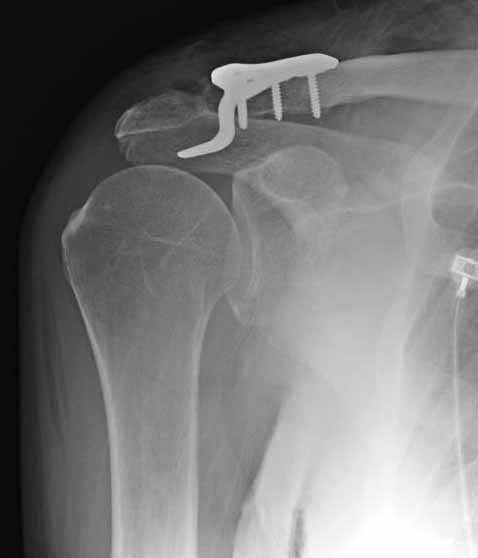

Я ставил польскую http://www.chm.pl/pliki/9878cd2387f303265ebad595b2519dce.pdf, но у них еще не опубликована методика

Но это не помешало успешно пациента прооперировать.

Еще раз спасибо Вам и всем форумчанам за внимание к теме и помощь.

1.JPG

60KB (62415 bytes)

foto

2.JPG

foto 3

3.JPG

foto 4

4.JPG

foto 5

коллаж у меня не получился, пришлось отдельно рентгенограммы присоединить :-))

5.JPG

15KB (16356 bytes)

Замечание понял, спасибо и нормальные рентгенограммы, молодец!

Во вторых, это хорошо что нашли длинную пластину, я об этом писал "пластина короткая, не покрывает медиальный диафизарный фрагмент ключицы", и у нас не получилось, пластина не выдержала...